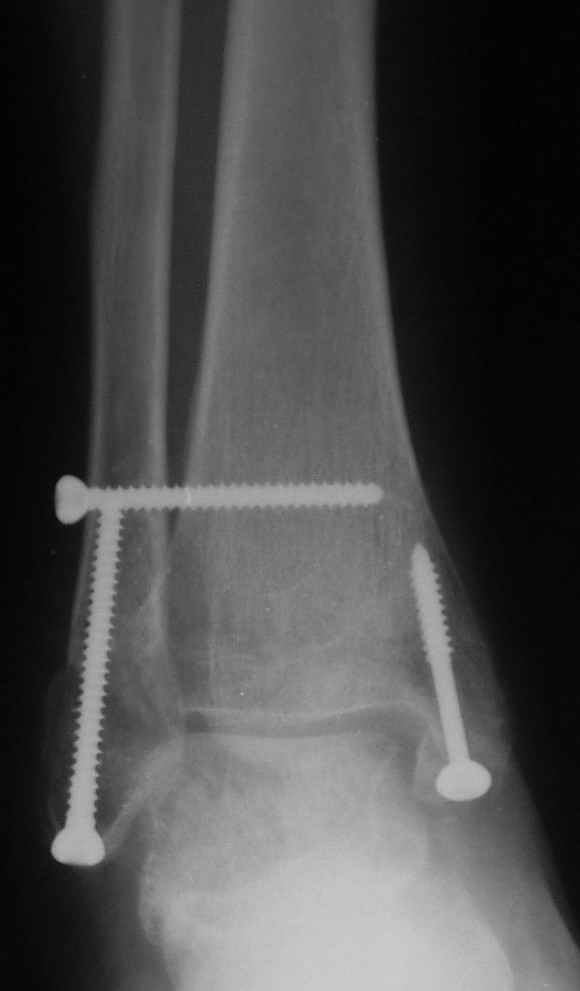

Ниже рентгенограммы

12 января прямой

|

12 января боковой

12 января трехчетвертной

Риторический вопрос - в каком руководстве рекомендован такой способ остеосинтеза наружной лодыжки?

Очевидно, такой результат операции был запрограммирован. При невосстановленной длине и практически нефиксированной малоберцовой кости (этот кортикальный винт - как карандаш в стакане), при неустраненном подвывихе, невправленной и тоже нефиксированной внутренней лодыжке нет стабильной вилки сустава. Если такую операцию сделать даже сразу, а не через 4 месяца, то результат ожидаем

Вариант с артродезом уже обсудили. Хотя, после увиденых снимков, пессимизм насчет восстановительной операции у меня, например, несколько уменьшился. Особенного уж какого-то остеопороза не видно даже на январских снимках. Можно черед мини-доступы убрать винты, аппаратом вправить малоберцовую кость, устранить подвывих стопы. Ну а дальше фиксировать малоберцовую пластиной сзади. А может, и напряженной Y-спицей попробовать - Анатолий Федорович, как Вы полагаете? Внутреннюю - то, что осталось, если уже не получится сделать спицами и проволокой, то что-то типа пластики дельтовидной связки. А может, и не трогать ее вовсе... В общем, выбор непростой,

много факторов надо взвесить.

Если до сих ничего не сделано, с артродезом сустава в данный момент я бы повременил, на выставленных январских снимках хорошо сохранившийся сустав, а в "мортиз" (трехчетвертной) и на боковых снимках не менее 5 мм укорочение малоберцовой кости. Косые переломы лучше фиксировать пластинами, как то мы разбирали случай, где было отмечено, что это закон "таранная кость всегда следует за малоберцовой".

В данном случаи я бы уговорил больного на реконструкцию, для этого после удаления шурупов, спереди очистить от рубцов синдесмоз, несросшуюся наружную лодыжку - остеотомия по линии перелома и компрессирующий (lagging technique) кортикальный шуруп 3.5 мм по поперечнику остеотомии. Следующий этап - восстановление длины малоберцовой за счет удлинения, сделать поперечную остеотомию где-то на уровне сантиметр выше вашего синдесмозного шурупа, наложить длинную пластинку, прикрепить пластину за дистальный конец двумя или тремя шурупами; сохраняя контакт пластины с костью, имеющимся

compression&tension device AO system (при отсутствии любой lamina spreader подойдет, создать дистанцию между пластиной и шурупом, проведенным проксимальнее пластины) толкая проксимальный отдел пластины, низвести пластину, мортиз рентгенограмма подскажет на сколько. Если заранее сделать предоперационный план (ренгенограмма другой стороны), тогда точно можно определить, на сколько вам необходимо сделать поперечную остеотомию малоберцовой кости, для закрытия создавшегося дефекта.

Убедившись, что желаемая длина восстановлена, окончательная фиксация пластины, при этом через пластину пару 3.5 мм шурупов на синдесмоз, предпочтительно в четыре кортекса и оставить на 3 мм длиннее, если под нагрузкой синдесмотический шуруп сломается, сломанный конец легче удалить с медиальной стороны.